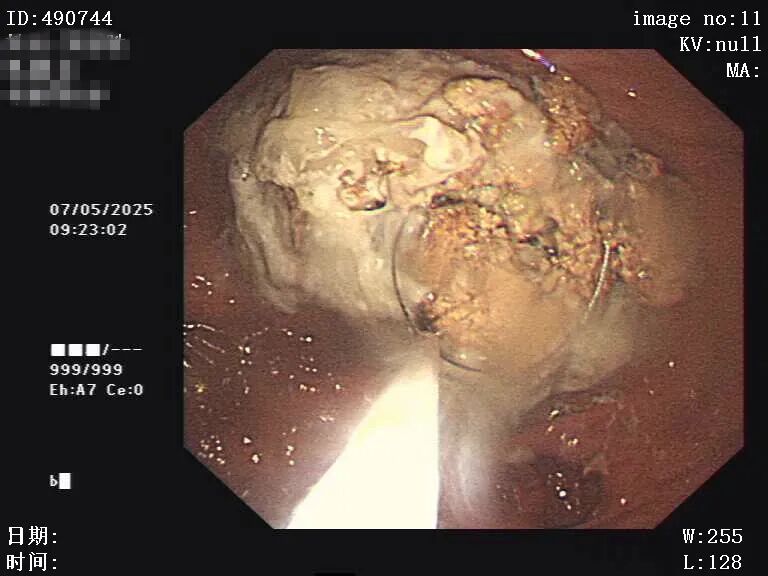

图片

4月29日胃镜检查:胃潴留及胃石形成